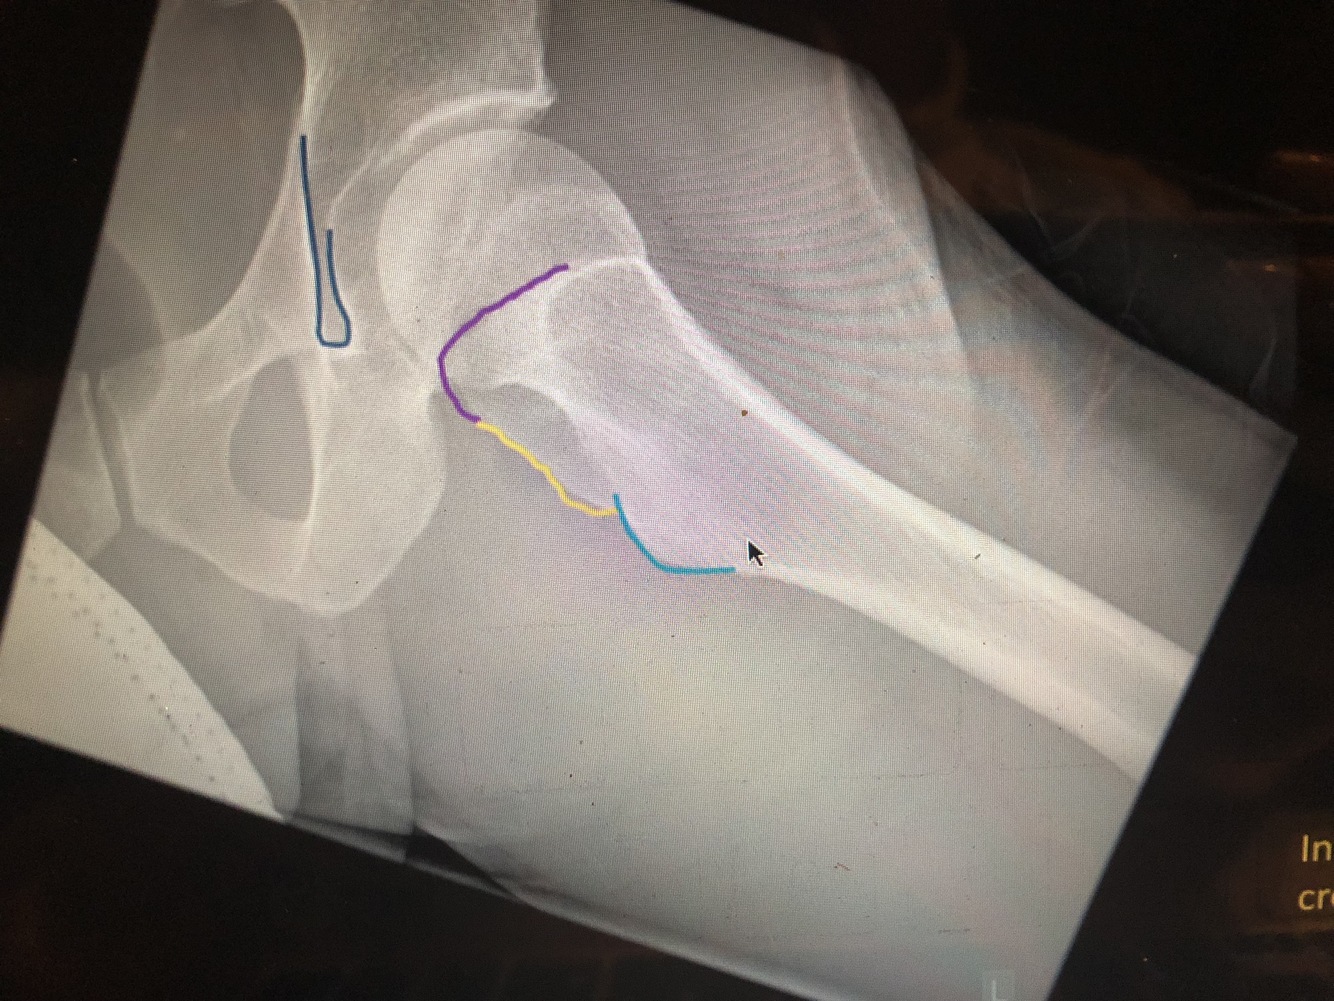

What is the red line?

most lateral part of Kohler’steardrop is the medial margin of the acetabulum

What is the green line?

The superior portion of the acetabulum has the thickest cortex

What is the orange line?

Superolateral margin of the acetabulum

What is the blue line?

Inferior portion of the acetabulum

What is the purple line?

The posterior rim of the acetabulum is more lateral.

What is the yellow line?

The anterior rim of the acetabulum is more medial. (not completely seen)